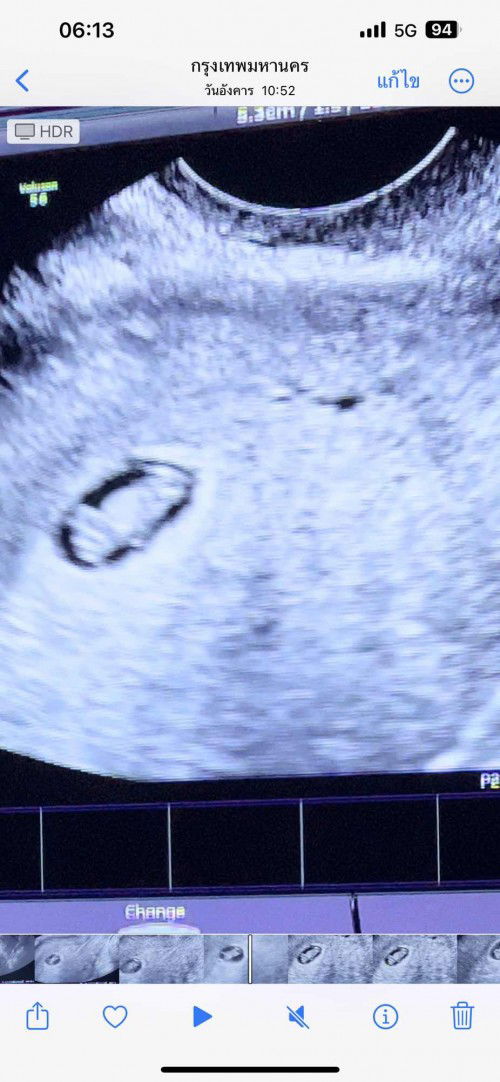

อุลตร้าซาวด์ วันที่ 14 ก.พ 66 น้องหัวใจยังเต้นปกติ  พอมาอุลตร้าซาวด์ วันที่ 18 ก.พ 66 หมอบอกน้องหัวใจไม่เต้นแล้ว 😭😭

ท้องใหม่ก็ต้องรอประจำเดือนมากี่รอบค่ะ เราจะนับวันไข่ตกยังไง #ขอบคุณสำหรับคำตอบค่ะ